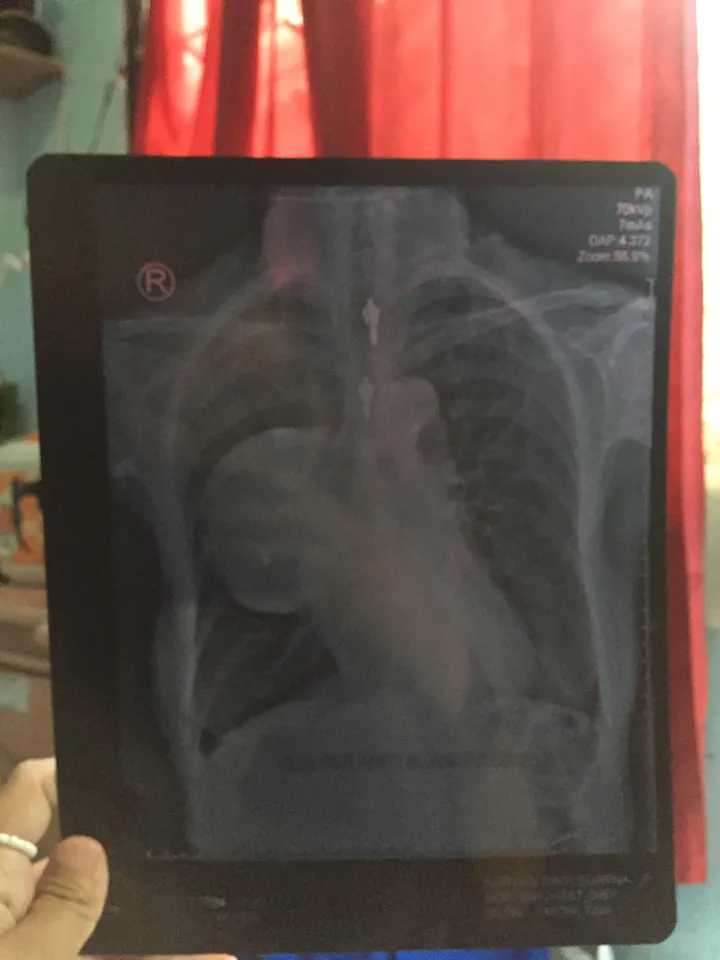

Meskipun tisu yang dijualnya hanya seharga dua ribu rupiah, sering kali orang-orang tidak tertarik membeli. Penghasilannya yang kecil, seringkali untuk makan aja tak tercukupi.Sudah lebih dari 8 tahun, anak Ibu Suryati menderita sakit paru-paru yang kronis. Kondisi fisiknya semakin melemah, sehingga ia tidak dapat bekerja dalam pekerjaan yang lebih berat.

Mereka tinggal bersama di sebuah rumah kontrakan yang harganya 700 ribu rupiah per bulan, namun keadaan mereka semakin sulit.Ibu Suryati sebenarnya membutuhkan kemoterapi untuk pengobatan penyakit yang dideritanya, namun karena keterbatasan biaya, pengobatan tersebut terhenti.